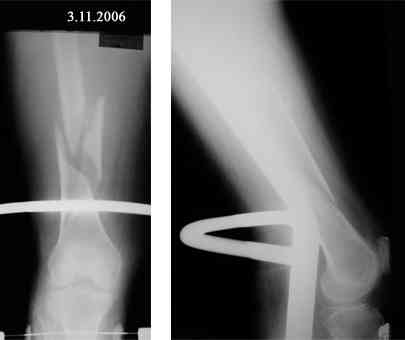

Представляю вашему вниманию снимки в динамике